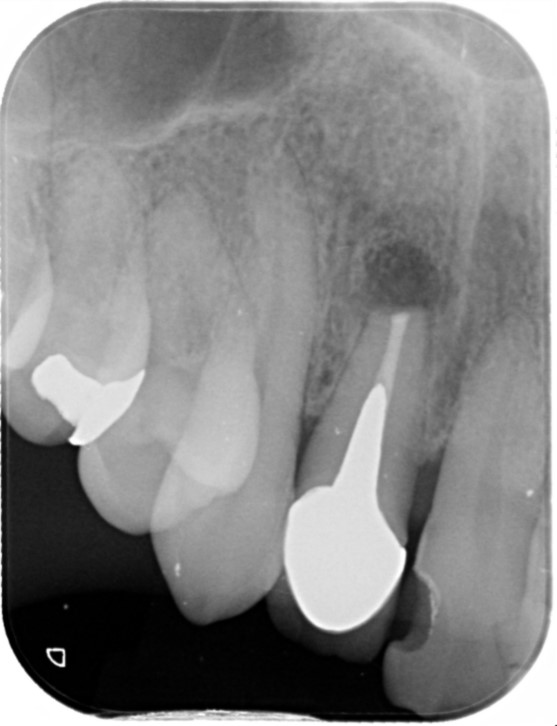

2023/1 根に穴が開いていました。

2023/8 根っこの治療が終わり、しっかり土台ができました。

治療部位 | 右上5番 |

費用 | 約93000円 |

治療期間 | 7ヶ月 |

マイクロスコープ、ラバーダムを使用して根管治療を行いました。